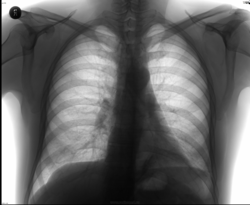

Молодой человек, 45 лет. Кашель с мокротой. Анализа крови нет. Температура была, под 40, три дня, две недели назад. Тогда пропил три дня сумамед. Коллеги, интересует мнение по снимкам. И Ваше Rg-заключение по ним.

Спасибо Всем за комментарии! Сам написал пневмонию слева, в нижней доле. С признаками гиповентиляции. Случай привёл для примера логической цепочки построения, для памяти того, что уже видели, читали и снова недавно вспомнили, если забывали...

Очень нравится как наш коллега написала: "Цитируя себя, любимую: Гиповентиляции левого легкого(сближение ребер, а значит и уменьшение межреберных промежутков, некоторое снижение прозрачности легкого, некоторое высокое стояние купола диафрагмы, некоторое смещение средостения)" Кое-что здесь присутствует, в большой мере, и значит не исключЁн...

Центральный рак слева

Мне кажется за тенью сердца, в S8, S9 инфильтрация легочной ткани в виде остаточных изменений.

Сегментарная пневмония в S 9 слева в ст. неполного разрешения.

Полисегментарная пневмония слева в S8 и в S5. И там же субсегментарные ателектазы.

данные представленных R-грамм расцениваю как левостороннюю н/долевую сегментарную пневмонию в фазе разрешения с исходом в локальный пневмофиброз.

А что на самом деле, автор? Не понравилось смещение средостения и дополнительные тени в проекции левого корня на боковом снимке. Архив был у пациента?

Прозрачность плеврального синуса слева снижена, значит там может быть гиповентиляция.